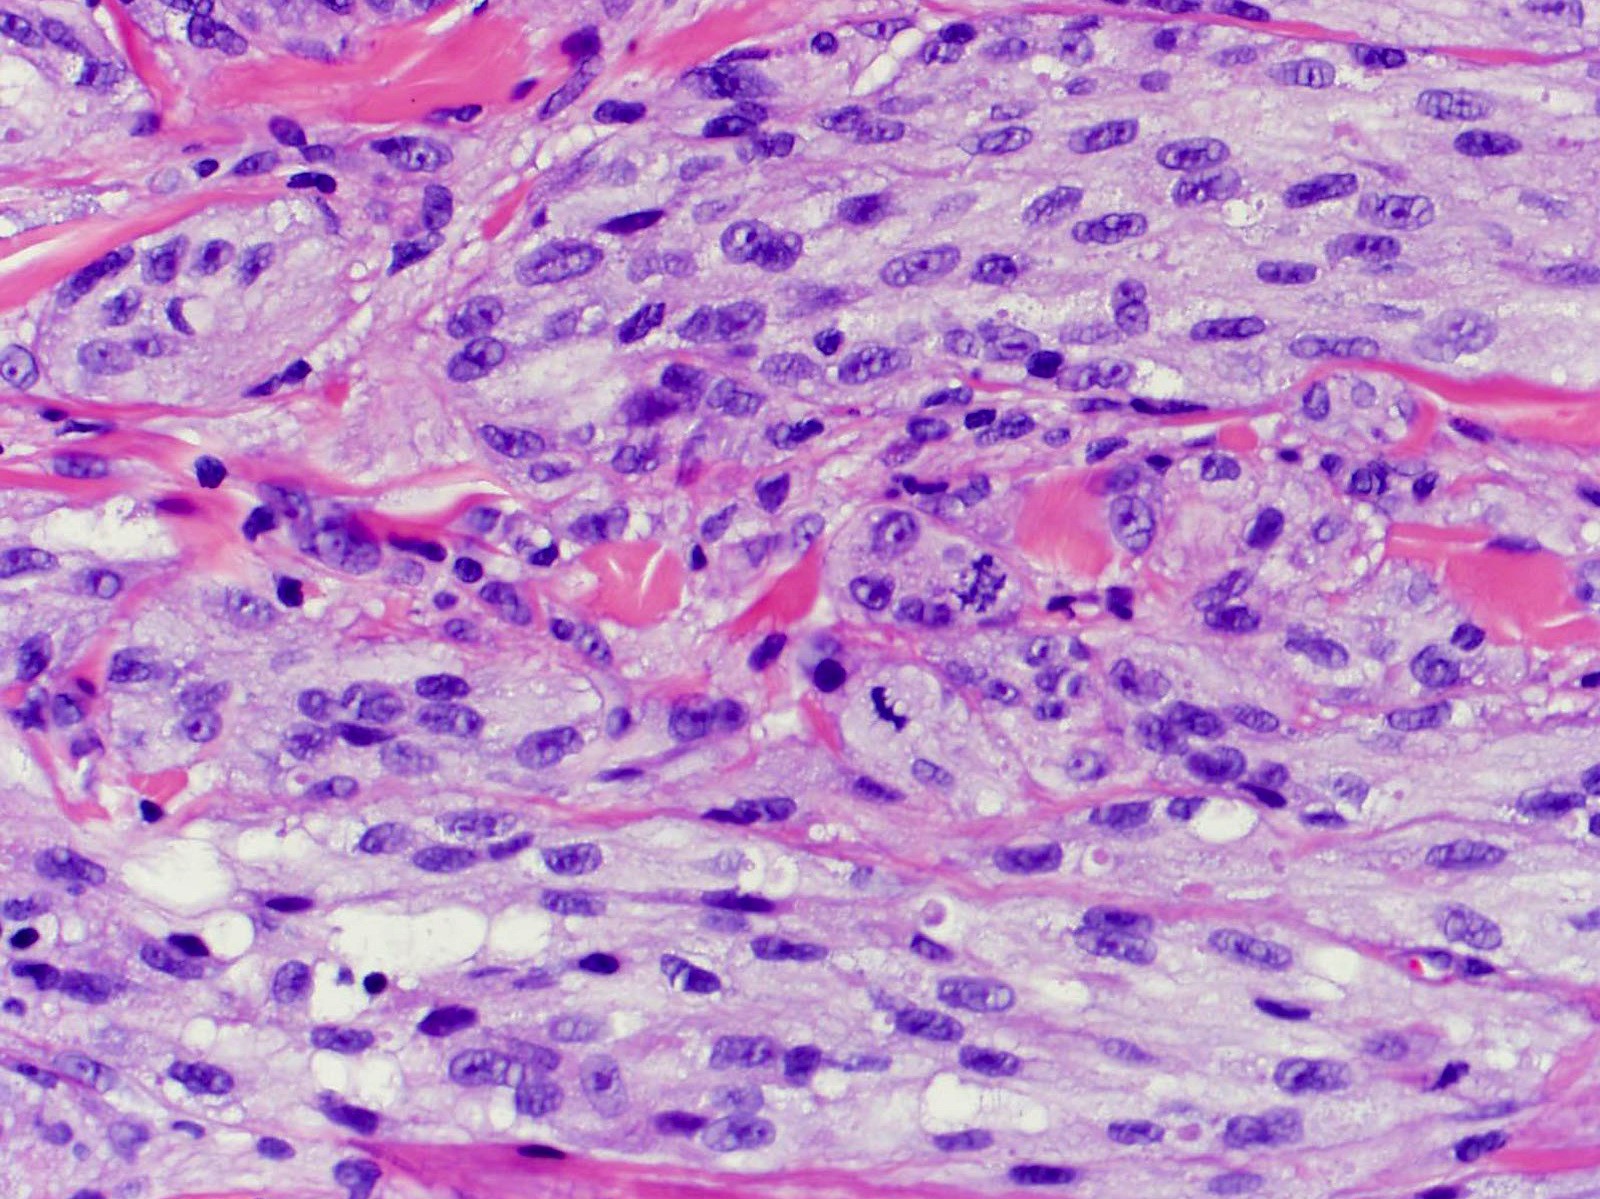

Microscopic (histologic) description

- Large polygonal cells with abundant eosinophilic granular cytoplasm and small, central nuclei

- Lysosomal macroinclusions (pustulo-ovoid bodies of Milian) are usually present (J Cutan Pathol 2007;34:405)

Microscopic (histologic) images

Contributed by Jarish Cohen, M.D., Ph.D.